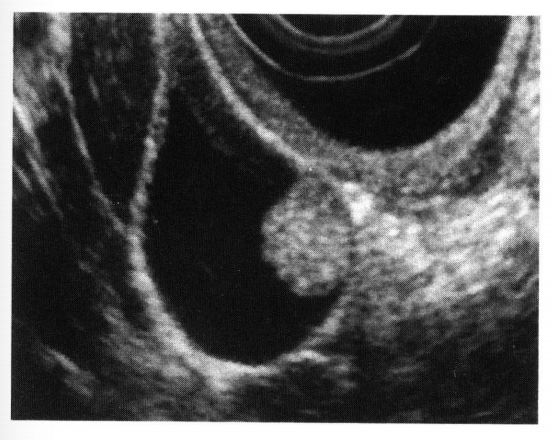

医師が胆嚢ポリープを心配している場合は、ポリープとそのサイズを診断するための検査を行うことがあります。考えられるテストは次のとおりです。

直径が 1/2 インチ未満のポリープの場合、医師は定期的な超音波検査をスケジュールして、癌を示す可能性のある変化がないか成長を監視する場合があります。医師は腹部超音波検査または内視鏡超音波検査を推奨する場合があります。

胆嚢ポリープと診断された場合、医師は超音波検査でポリープを観察することを推奨する場合があります。がんの可能性が高い場合、または胆石を患っている場合、医師は胆嚢を外科的に切除することを勧める場合があります。